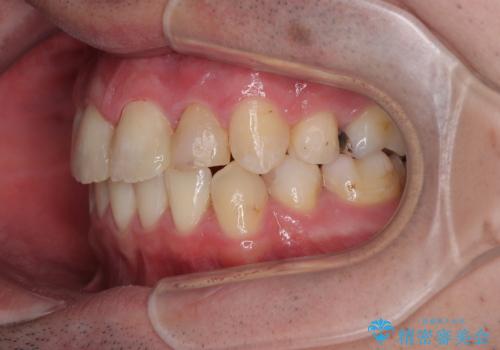

口元はやや突出感があったため、上下左右の第一小臼歯4本を抜歯してワイヤー矯正にて抜歯矯正を行うこととしました。

また、左右ともに最後臼歯が交叉咬合になっており、外側に飛び出している上顎の最後臼歯を補助装置を利用して、積極的に内側に引き込むようにしました。